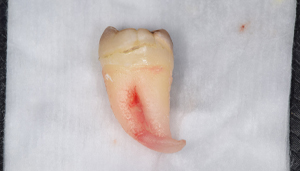

- 抜歯前写真(レントゲン)

- 抜去歯の写真(CT画像)

| 年齢 | 40代・男性 |

|---|---|

| 主訴 | 右下奥歯が痛い |

| 親知らずの生え方 | 斜めに生えている |

| 抜歯時間 | 30分 |

| 費用 | 約6,000円(保険診療、CT代含む) |

| 抜歯内容 | レントゲン上で右下の親知らずが大きく虫歯になっており、斜めに生えていることもあり患者様の希望により抜歯することとなりました。 当日は痛みがあったため抗生剤と鎮痛剤にて炎症を抑え、後日歯ぐきを切開し、抜歯を行いました。 レントゲン上でも分かるように親知らずの根が二つに分かれており根が折れてしまう可能性がありましたが、このケースでは事前にCTを撮影し、歯の位置、根の方向を確認していたため根が折れることなく抜歯ができました。 術後数日は腫れと痛みがありましたが、薬の服用で抑えることができ、1週間後の糸取りの際には痛み、腫れともになくなっていました。 |